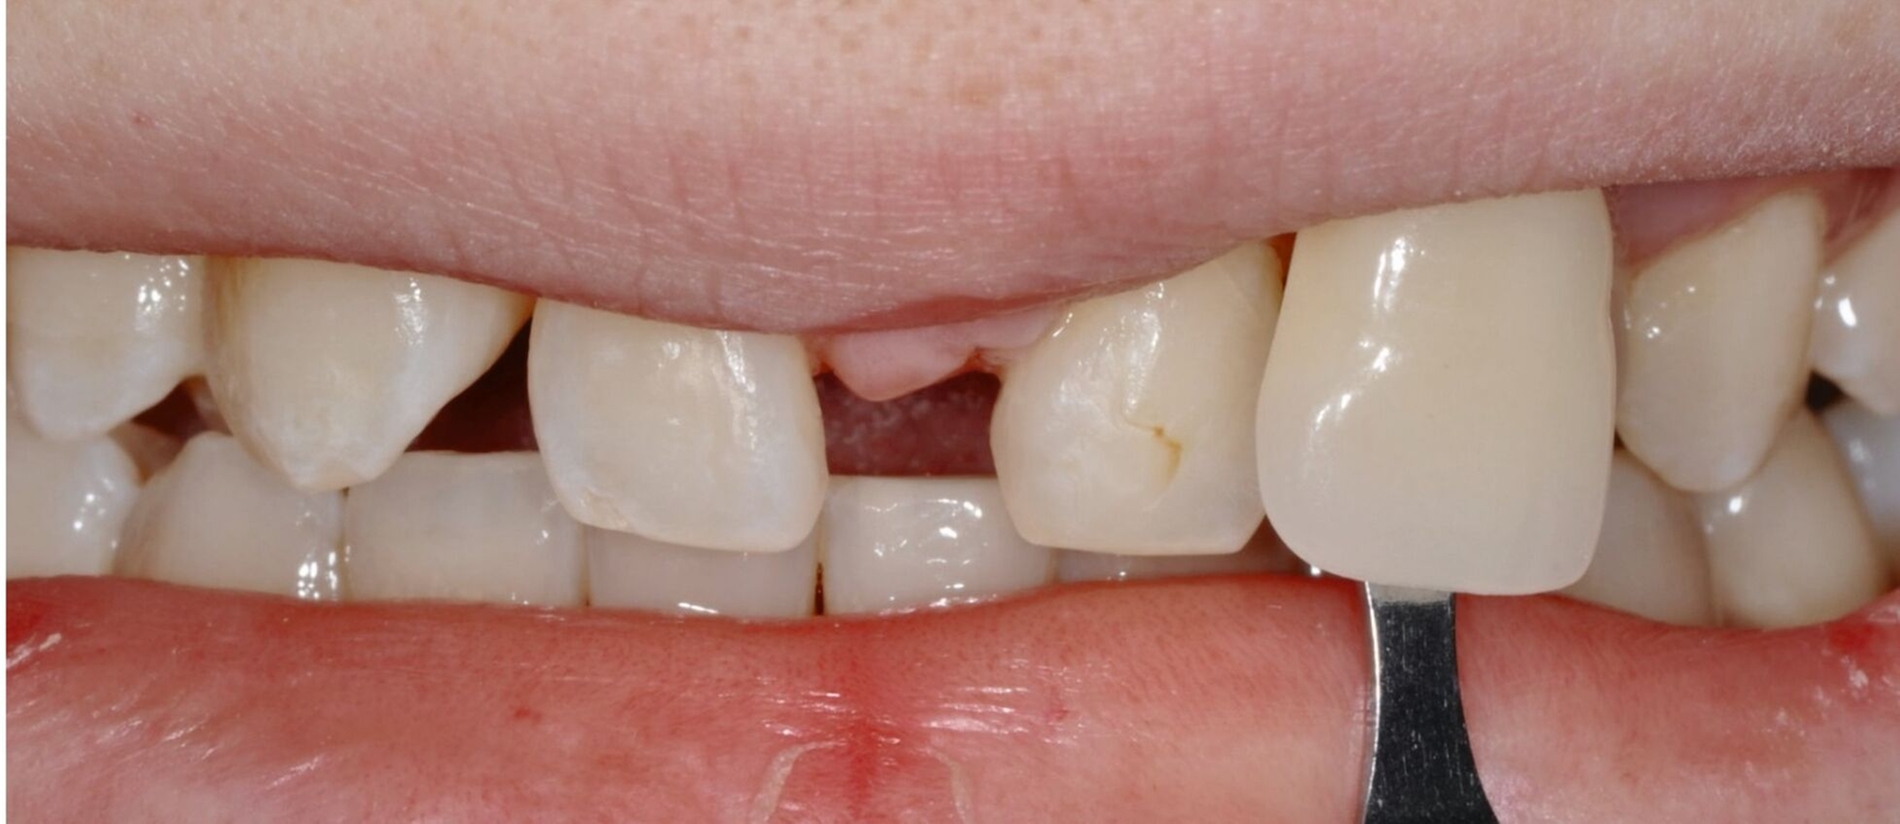

Auch bei einer Kontrolluntersuchung drei Jahre nach restaurativer Therapie sind die Versorgungen in situ, intakt, und das Parodontium zeigt keine entzündlichen Veränderungen. Trotz Anfertigung der Retentionsschienen fällt ein beginnendes Diastema mediale auf (Abbildung 4). Der Patient gibt auf Nachfrage an, die Schienen nicht regelmäßig getragen zu haben. Ihm wird die Möglichkeit eines Diastemaschlusses durch eine erneute Zahnformkorrektur angeboten. Da ihn die entstandene Lücke jedoch subjektiv nicht stört, entscheidet er sich zunächst gegen eine restaurative Korrektur.